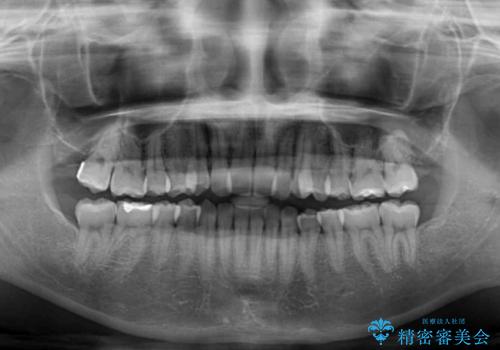

前歯のクロスバイトをインビザライン矯正で改善

- 前歯のデコボコと上下のクロスバイトを気にして来院された患者様です。

インビザラインを用い、IPR(歯と歯の間を削る)と歯列全体を拡大させることで、歯並びを整えていくこととしました。

上の前歯が下の前歯を乗り越える際、奥歯がほとんど咬めない時期があり、乗り越えた後も、インビザライン特有の奥歯の咬みにくさが続きました。

咬み合わせ改善のために治療期間を要しましたが、最終的に奥歯はしっかりと咬めるようになりました。